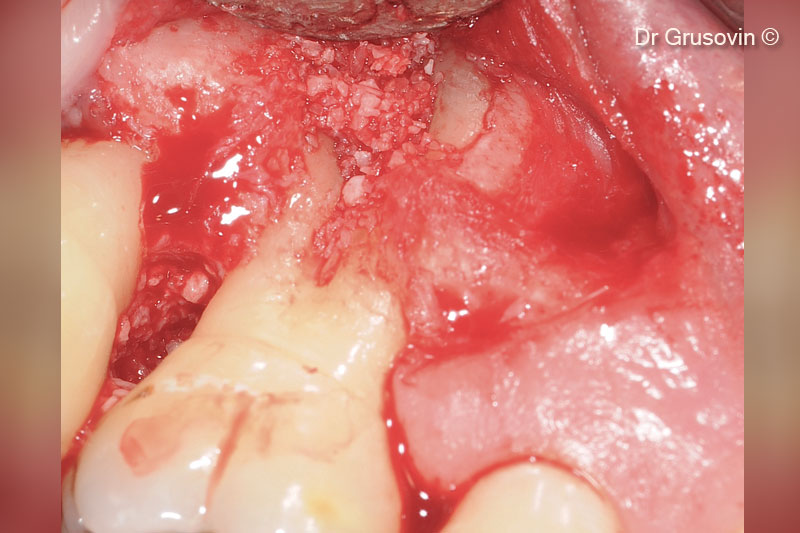

5. OsteoBiol® Gen-Os® inserted vestibularly